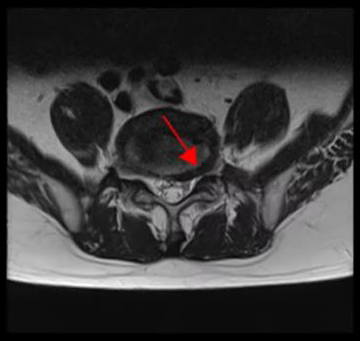

<5-1번 디스크 파열>

이 환자분의 허리 MRI를 보면 4번, 5번 오른쪽에 심한 추간공협착증과 2단계의 척추전방전위증이 있는데, 특히 척추전방전위증 때문에 추간공이 많이 좁아져 있는 상태입니다. 또 왼쪽의 다른 마디에 디스크 파열이 있으나 환자분이 왼쪽으로는 증상이 전혀 없는 것으로 보아 이 디스크 파열은 통증을 일으키지 않는 무증상의 디스크 파열입니다.